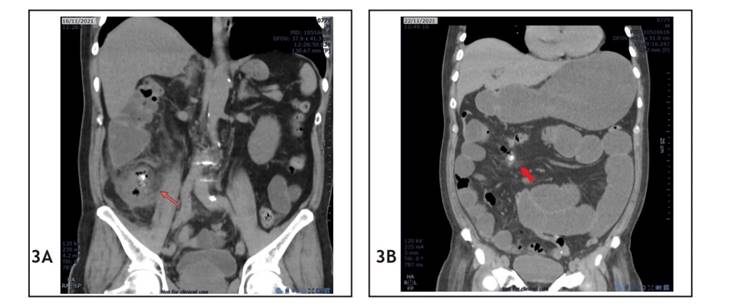

A 77-year-old male was admitted to the emergency room of a public hospital in Lima on November 16, 2021 (day 1), complaining of pain in the hypogastrium for four days, with a history of hypertension and cholecystectomy. After being examined, the patient was diagnosed with acute appendicitis, confirmed by a CT scan which provided the following findings (Figure 3A): “cecal appendix thickening, 17 mm in diameter, with appendicoliths and gas bubbles inside.” The tests revealed his leukocytes: 15,290/mm3. He was then scheduled for a laparoscopic appendectomy. During the operation, an appendiceal phlegmon with friable bowel loops were observed; therefore, it was decided to convert the operation into an open appendectomy. Adhesions were removed, with opening of Toldt’s fascia of the right paracolic gutter. A retrocecal, retroperitoneal, ascending, completely necrotic cecal appendix with necrotic mesoappendix was found; two coprolites were removed from the tip of the appendix, where 15 cc abscess was drained; and an appendectomy was performed. A Penrose drain with counteropening was placed at the appendiceal stump. During the postoperative period, a tree-day fast, ceftriaxone and metronidazole were prescribed.

During postoperative hospitalization, the patient made good progress: on the fourth postoperative day (day 5) he started a soft food diet and on the following day (day 6) a complete diet, which was well tolerated, with elimination of flatus and stools. On the sixth postoperative day (day 7), the patient experienced belching and abdominal distension, so a CT scan was requested (Figure 3B). The CT scan revealed the following findings: “thin intestinal loops dilated in both the jejunum and proximal ileum, with a maximum diameter of 41 mm and several air-fluid levels; rule out adhesions. At this level, a 9 mm loose hyperdense mass in peritoneal fat, surrounded by gas, with a morphology similar to an appendicolith and collapsed thick loops was detected, not seen in a previous control.” With this report, a medical board was held to evaluate the risk-benefit of a second surgical intervention versus conservative management. It was concluded that a surgical intervention would be the most beneficial option.

Figure 3 Case 2 CT scans. (A) Preoperative abdominal CT scan; the red arrow shows the appendicolith. (B) Abdominal CT scan on the sixth postoperative day; the red arrow shows the dropped appendicolith at the intestinal loops.